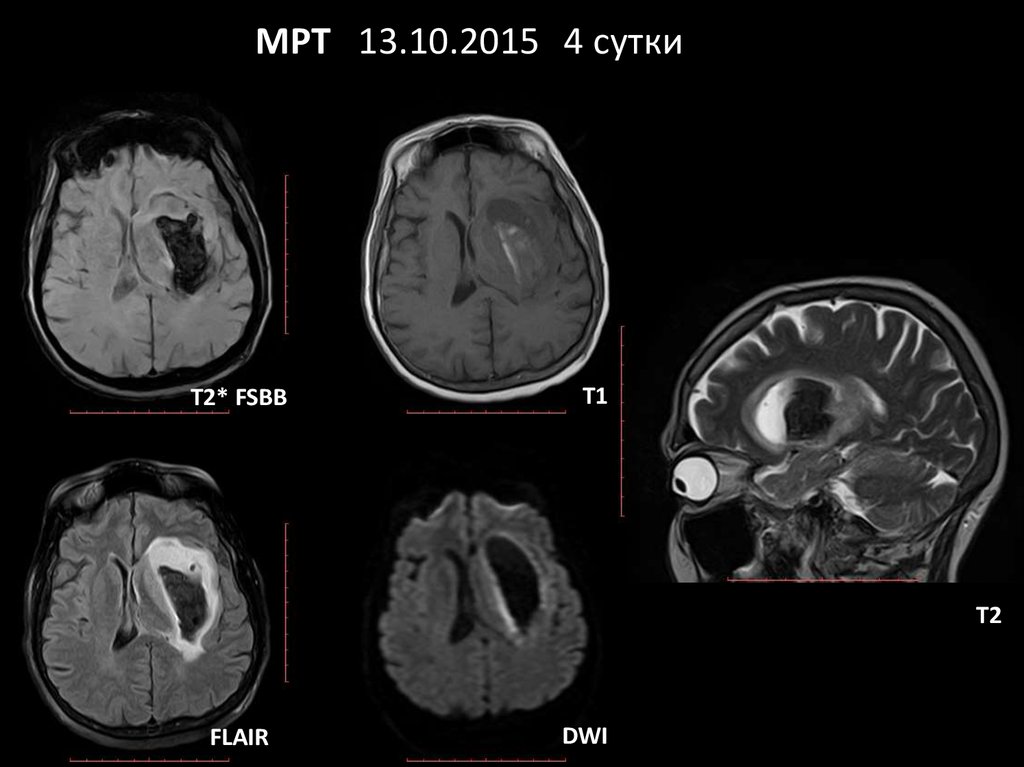

МРТ 13.10.2015 4 сутки

T2* FSBB

T1

T2

FLAIR

DWI